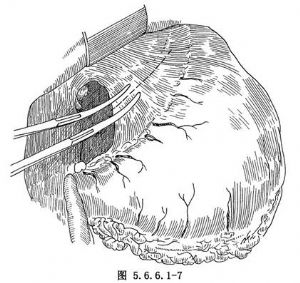

(3)游离胃:探查腹腔,如腹内无明显转移,在胃体上2/3与1/3交界处的小弯侧将胃肝韧带切开,再由相对应的胃大弯侧切开胃结肠韧带,用一条纱带越过胃后将胃向上牵引(图5.6.6.1-4)。继续切开胃结肠韧带,保留胃网膜右动脉,将韧带中的血管钳夹后切断结扎(图5.6.6.1-5)。切开胃脾韧带,切断结扎胃短动脉分支。在暴露术野时注意牵拉脾脏不能用力过大,以免撕裂脾脏(图5.6.6.1-6)。胃大弯侧游离足够以后,离断胃肝韧带,保留胃右动脉(图5.6.6.1-7)。在贲门下方附近的小弯侧摸到搏动的胃左动脉,用3把止血钳夹住,近侧两把,远侧1把,切断后先缝扎一道,再由其深部结扎一道(图5.6.6.1-8),缝扎胃侧血管断端。如此时胃左动脉近侧残端有出血,应先用指压住出血点,再请第一助手以拇指用力按压胸主动脉即可止血,用吸引器将积血迅速清除后,即可从容寻找到出血处予以处理。小弯侧游离完后,在离断贲门之前,请麻醉师将胃管连接在吸引器上持续吸引,将胃内容物尽量吸净,如此可以减少污染并方便吻合操作,吸引完后将胃管向外拔,使其尖端置于贲门上方3~4cm处。用大号直止血钳夹住贲门切断(图5.6.6.1-9)。胃侧断端用中号丝线贯穿缝合,再将浆肌层对拢间断缝合。食管侧断端用贯穿缝合封闭后用阴茎套保护之。将游离完毕的胃提至胸腔。